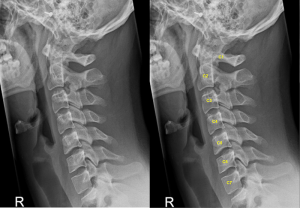

Thoái hóa là tình trạng mòn sụn khớp và đĩa đệm theo thời gian, thường gặp ở người trung niên, gây đau vùng cổ, cứng khớp và hạn chế vận động. Trên phim X-quang, có thể thấy hẹp khe khớp hoặc gai xương nhỏ. Điều trị gồm vật lý trị liệu, chỉnh tư thế và dùng thuốc giảm đau.

Gai xương thường hình thành như một phản ứng bù trừ của cơ thể trong quá trình thoái hóa cột sống cổ. Sự phát triển của các gai này có thể khiến bề mặt khớp cọ xát, gây đau và viêm tại chỗ. Khi gai xương lớn dần, chúng có thể thu hẹp không gian trong ống sống cổ, chèn ép tủy sống và rễ thần kinh, dẫn đến rối loạn vận động hoặc cảm giác ở vùng cổ, vai và chi trên.

Tình trạng thoái hoá cột sống cổ

(Nguồn: Bệnh viện Hồng Ngọc)